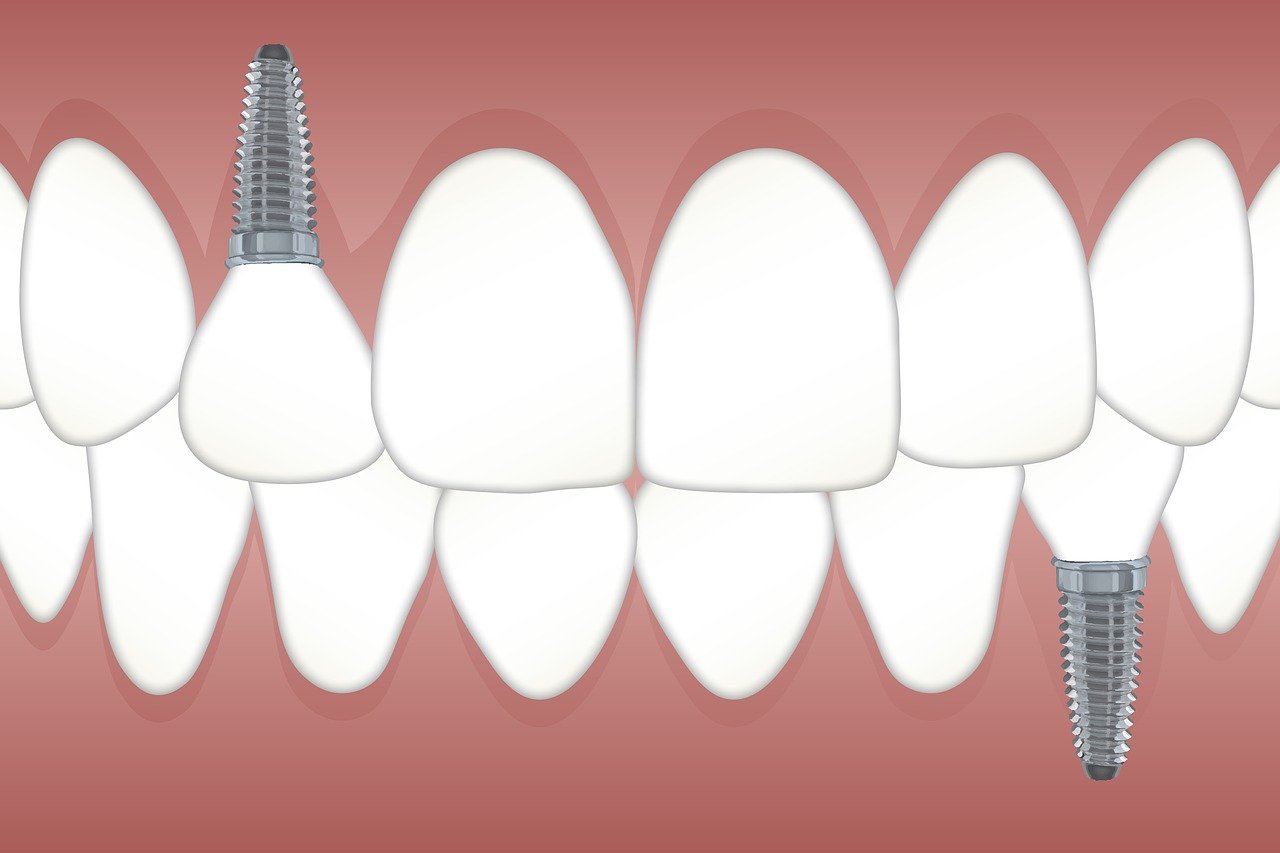

L'implant dentaire est un dispositif en titane ressemblant à une vis, qui sert de racine artificielle à une prothèse dentaire. Son rôle est de remplacer une dent manquante et d'assurer toutes les fonctions de la racine naturelle, en servant d'intermédiaire entre l'os de la mâchoire et la prothèse. Il permet la pose d'une prothèse amovible (dentier) ou d'une prothèse fixe (bridge, couronne, prothèse complète, etc.).

Si vous avez perdu une ou plusieurs dents, l'implant dentaire peut vous apporter un confort considérable au quotidien. Il est recommandé de consulter un spécialiste en implantologie ou votre chirurgien-dentiste afin de déterminer le type d'implant le plus adapté à vos besoins.

La pose d'un implant se réalise généralement sous anesthésie locale. Les complications sont rares, mais peuvent inclure :

Les implants dentaires sont conçus pour durer plusieurs décennies, voire toute une vie. Leur longévité dépend cependant de nombreux facteurs : l'état de santé général du patient, la qualité de l'implant, et surtout l'entretien et l'hygiène bucco-dentaire au quotidien.